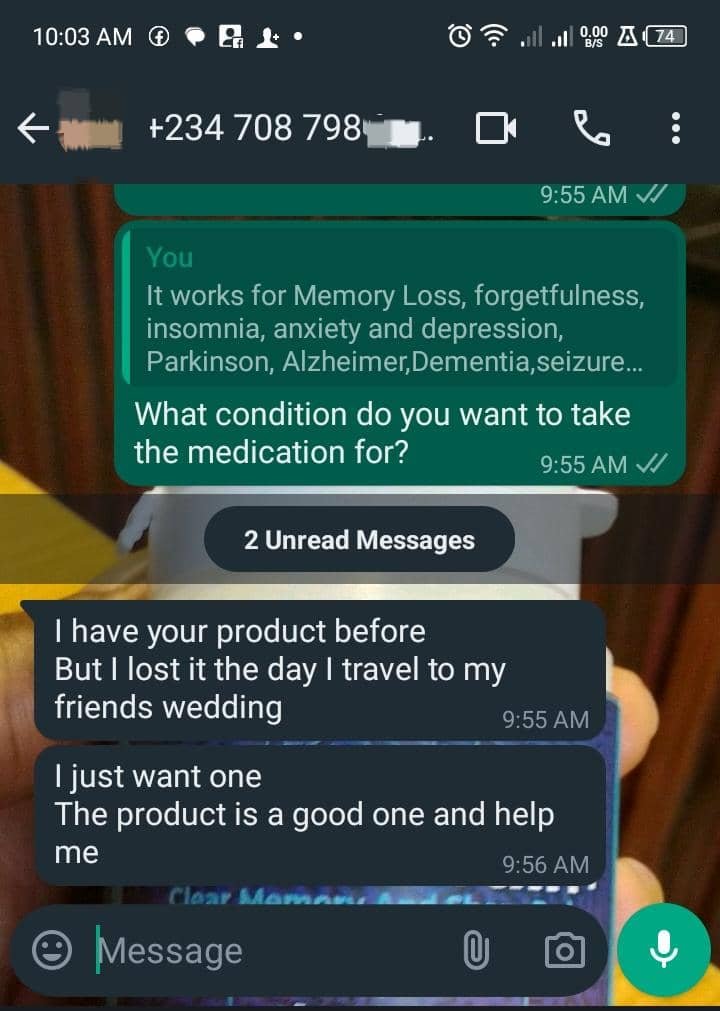

See what people are saying about MemoBrain+

Mrs Doris started remembering names she had forgotten in a long time… 3 days after taking this MemoBrain+

See the testimony below:

She’s not the only one

Don’t take my words for it…

See what people like you are saying about MemoBrain+

"The Product is a good one"

"There are lots of improvement"